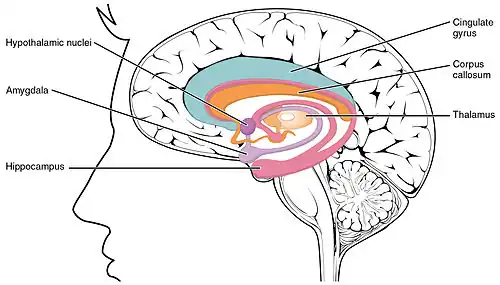

White matter consists of nerve fibers (axons) covered by a substance called myelin that insulates and protects them.[3] The axons extend from nerve cells (neurons) and transmit nerve impulses throughout the body.[3]

LENAS is seen with damage to the white matter and axons within the brain. The external human LENAS brain shows findings in several major structures. There is mild atrophy of the frontoparietal regions of the brain and a mild reduction of the thalamus and rostral (front) part of the caudate nucleus (which is located in an area of the brain called the basal ganglia).[5] Abnormalities in the frontal, frontoparietal, and temporal lobes are most severe and predominant with LENAS and asymmetry of the cerebral hemispheres has sometimes been found.[5] LENAS also may show moderately enlarged lateral ventricles and atrophy in corticospinal tracts as well as in the pons.[5]

The area where it is seen to be the most pronounced abnormalities appear in the white matter below the pre- and postcentral gyri that extend through the posterior limb of the internal capsule into pyramidal tracts of the brain stem.[5]

- The corpus callosum is variably affected.

- Reactive astrocytes and macrophages are present, but no inflammation appears.

- The cerebral cortex and basal ganglia are normal and contain no or only few spheroids.

- Within the cerebellum, there is a marked loss of Purkinje cells seen but cerebral white matter is normal.